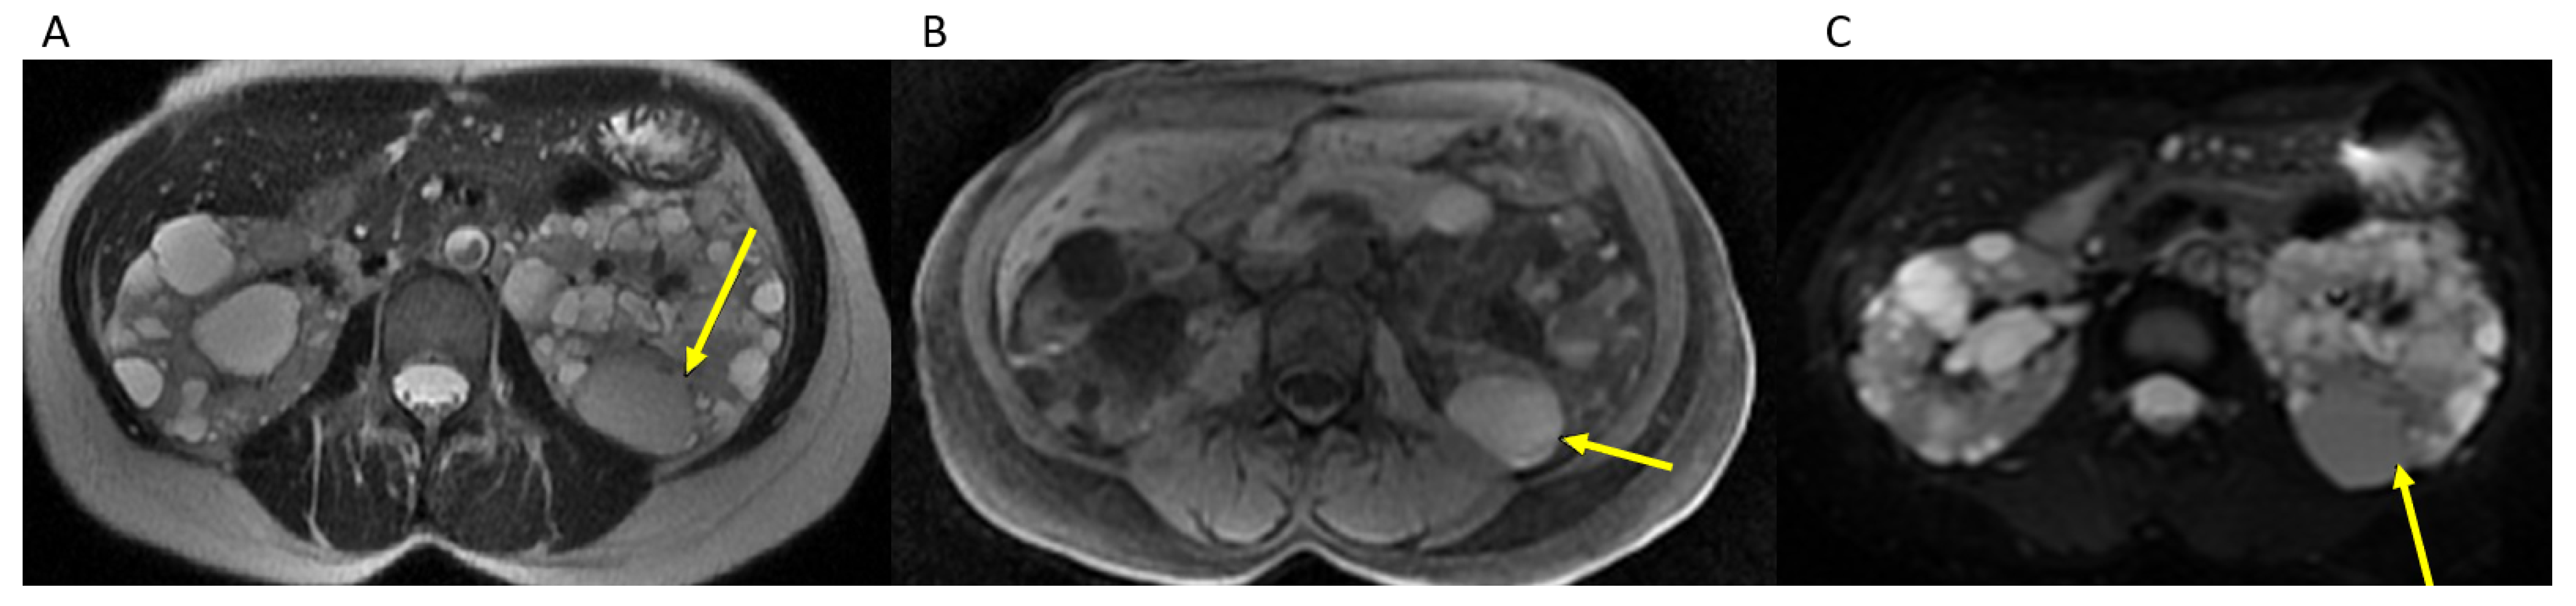

2.3. TKV Calculation